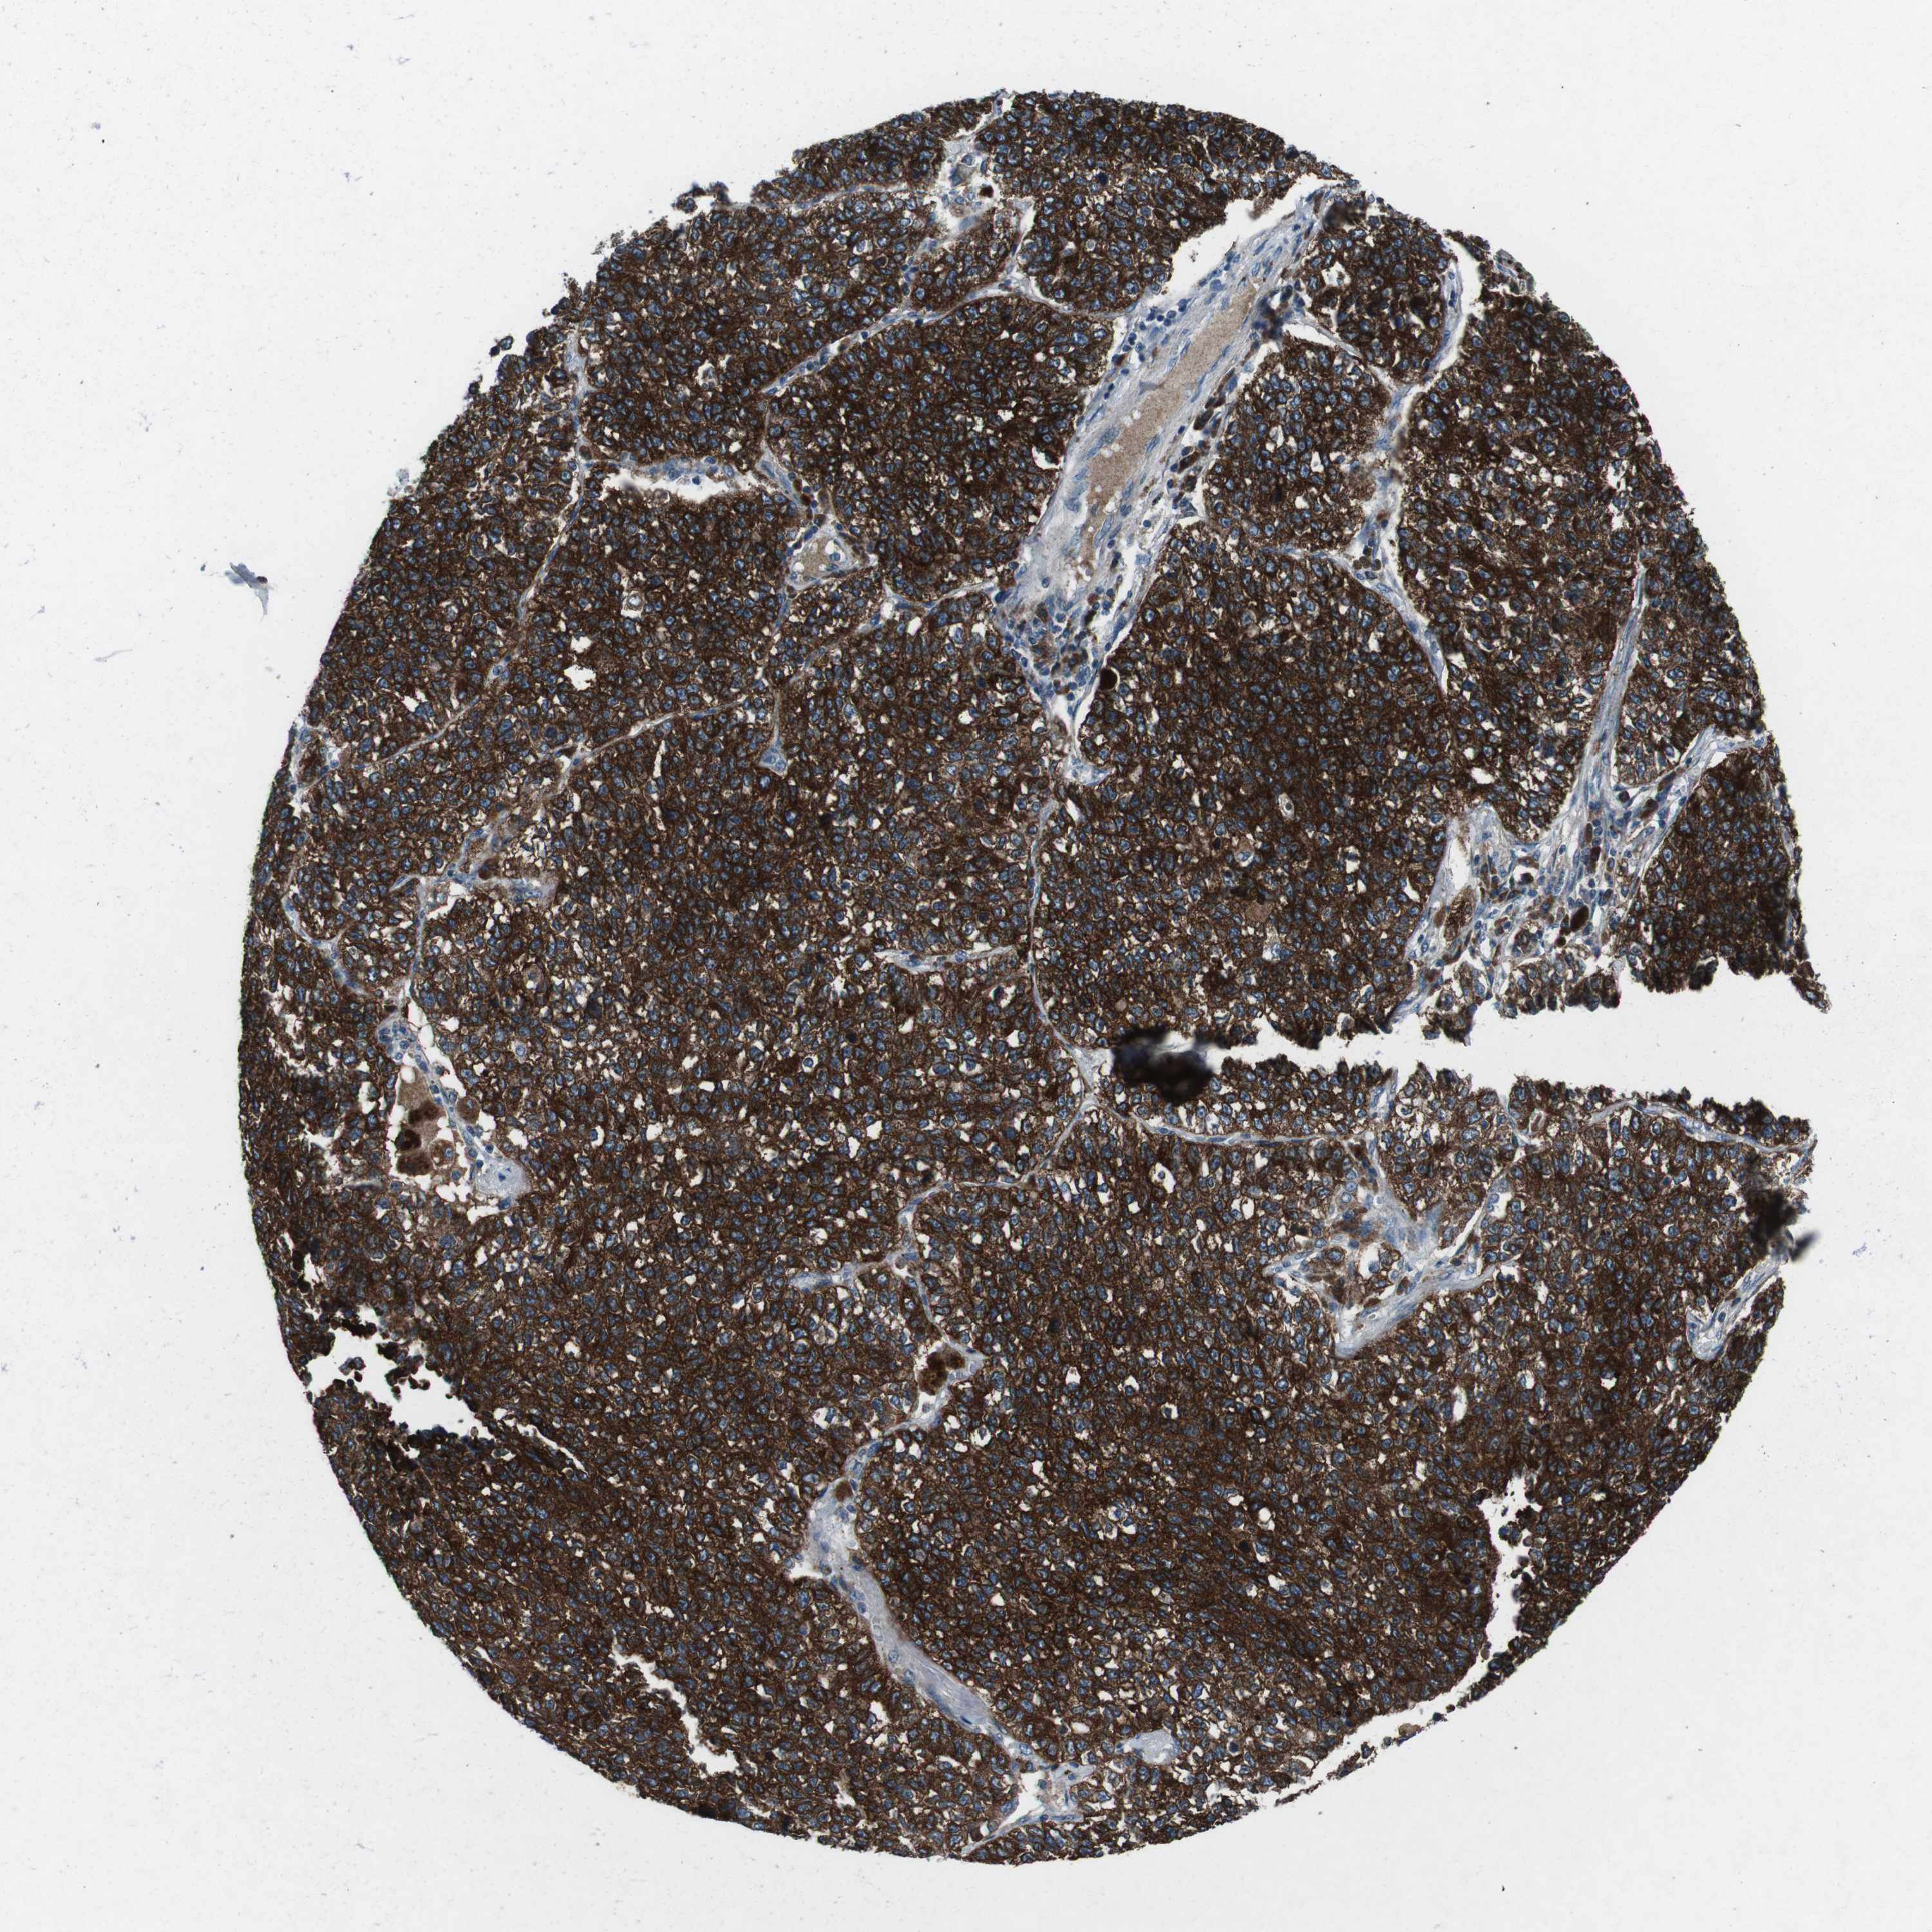

LUNG SQUAMOUS CELL CARCINOMA (TCGA) - Interactive survival scatter ploti

The Survival Scatter plot shows the clinical status (i.e. dead or alive) for all individuals in the patient cohort, based on the same data that underlies the corresponding Kaplan-Meier plots. Patients that are alive at last time for follow-up are shown in blue and patients who have died during the study are shown in red.

The x-axis shows the expression levels (FPKM) of the investigated gene in the tumor tissue at the time of diagnosis. The y-axis shows the follow-up time after diagnosis (years). Both axes are complimented with kernel density curves demonstrating the data density over the axes. The top density plot shows the expression levels (FPKM) distribution among dead (red) and alive patients (blue). The right density plot shows the data density of the survived years of dead patients with high and low expression levels respectively, stratified using the cutoff indicated by the vertical dashed line through the Survival Scatter plot. This cutoff is automatically defined based on the FPKM cutoff that minimizes the p-score. The cutoff can be changed by dragging the vertical line or by entering a cutoff value in the square labeled "Current cut-off".

Under the Survival Scatter plot the p-score landscape (black curve; left axis) is shown together with dead median separation (red curve; right axis). Dead median separation is the difference in median mRNA expression between patients who have died with high and low expression, respectively. It is calculated as follows: median FPKM expression of dead patients with high expression - median FPKM expression of dead patients with low expression. This is intended to aid the user in visually exploring custom cutoffs and the associated p-scores and dead median separation.

Individual patient data is displayed and can be filtered by clicking on one or more of the category buttons on the top of the page. Categories describing expression level and patient information include: high, low, alive, dead, female, male and tumor stages. The scale of the x-axis can be toggled between linear and log-scale by clicking on the "x log" button. Mouse-over function shows TCGA ID, patient information and mRNA expression (FPKM) for each patient.

& Survival analysisi

Kaplan-Meier plots summarize results from analysis of correlation between mRNA expression level and patient survival. Patients were divided based on level of expression into one of the two groups "low" (under cut off) or "high" (over cut off). X-axis shows time for survival (years) and y-axis shows the probability of survival, where 1.0 corresponds to 100 percent.

CDK16 is not prognostic in Lung Squamous Cell Carcinoma (TCGA)

Best expression cut offi

Based on the FPKM value of each gene, patients were classified into two groups and association between prognosis (survival) and gene expression (FPKM) was examined. The best expression cut-off refers the FPKM value that yields maximal difference with regard to survival between the two groups at the lowest log-rank P-value. Best expression cut-off was selected based on survival analysis .

When clicking on this number, the vertical dashed line indicating cut-off, the interactive survival plot, and the Kaplan-Meier curve will be adjusted to show results based on the best expression cut-off.

: 80.75

P scorei

Log-rank P value for Kaplan-Meier plot showing results from analysis of correlation between mRNA expression level and patient survival.

N/A

Average pTPM 96.0

Number of samples 489